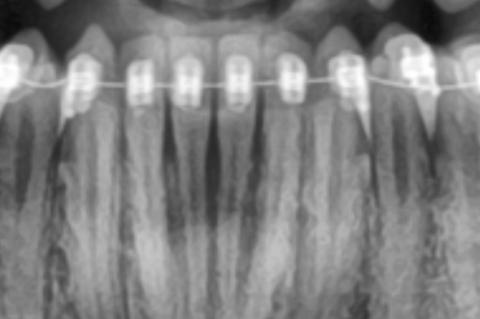

The X-ray image shows the lower front teeth with orthodontic braces in place. The tooth roots are visible, but the bone level around the roots appears reduced and uneven. There are darker areas between and around the roots, suggesting loss of supporting bone rather than healthy, dense bone.

This finding is especially important in patients undergoing orthodontic treatment.

This X-ray shows bone loss around lower front teeth during orthodontic treatment, a condition that requires close coordination between dentist and orthodontist. Early intervention can preserve tooth support and allow safe continuation of braces.